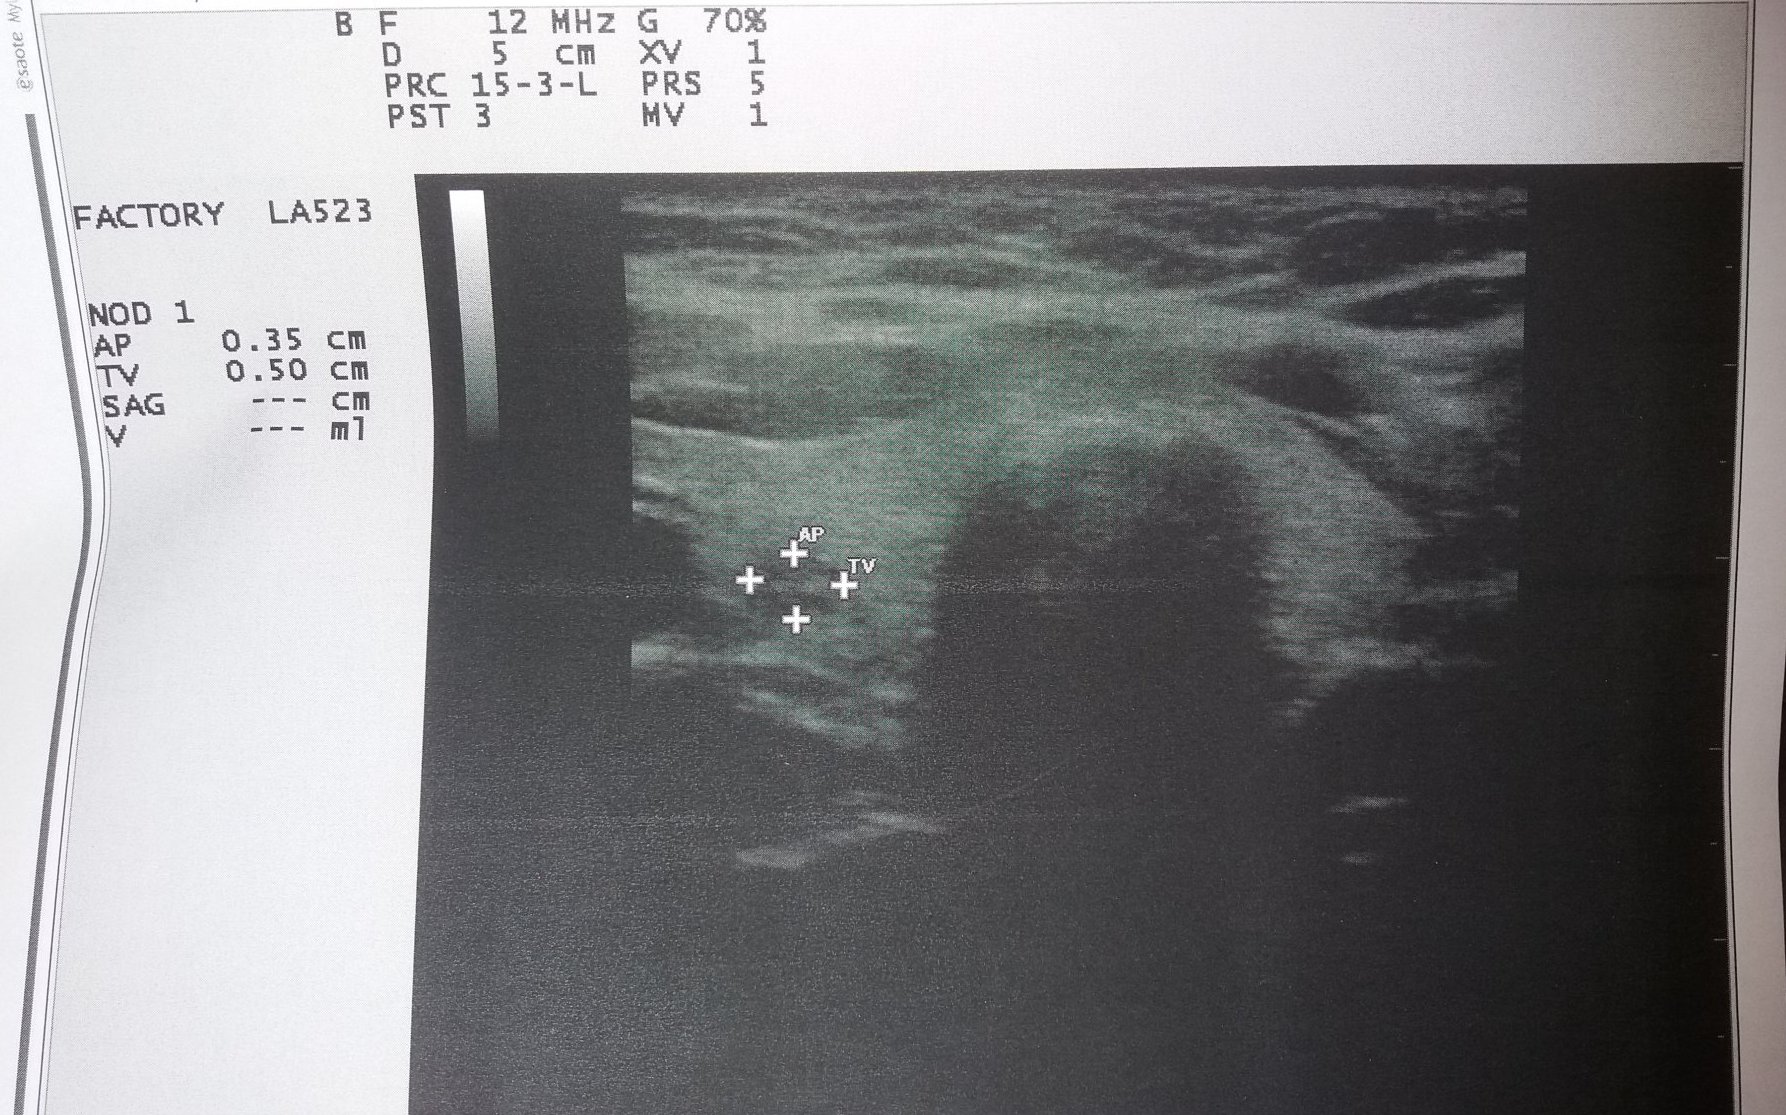

А това е ехографията:

Скрит текст:

Какви ли са тези "вълни" отгоре...

По това, че има въобще антитела. Едните са 29%, а другите 35% от реф стойности, което мисля не е никак малко. Някакъв вероятно начален процес е, но това тсх 5 ми се струва, че е стигнало с течение не на няколко месеца, а години. Разбира се, ехографията си е преди всичко доказателственият материал.

Твоите са доста по-надолу. Нищо чудно твоят японец да е позаспал в ремисия.😁 Колкото по-ниски антитела, толкова по-малко изменения, доловими на ехо. Макар че, май мибобо беше, има хаши, а не се виждат изменения на ехо (извинявам се, ако бъркам потребителя).

Официално никой още не ми е казал за "японска" диагноза... Joy Доколкото разбирам, една (вероятно немалка) част от ендокринолозите ще "изчакат" антителата да се повишат над референтните стойности, за да поставят диагноза Хашимото? Е, освен ако ехографията не е много зле...

И аз съм се замисляла реално дали има човек с 0,но на фона на една хипофункция веднага идва съмнението за Хашимото. То и затова ехото си е най-сигурният метод, макар че добър ендо тр дори и само с опипване да го установи.